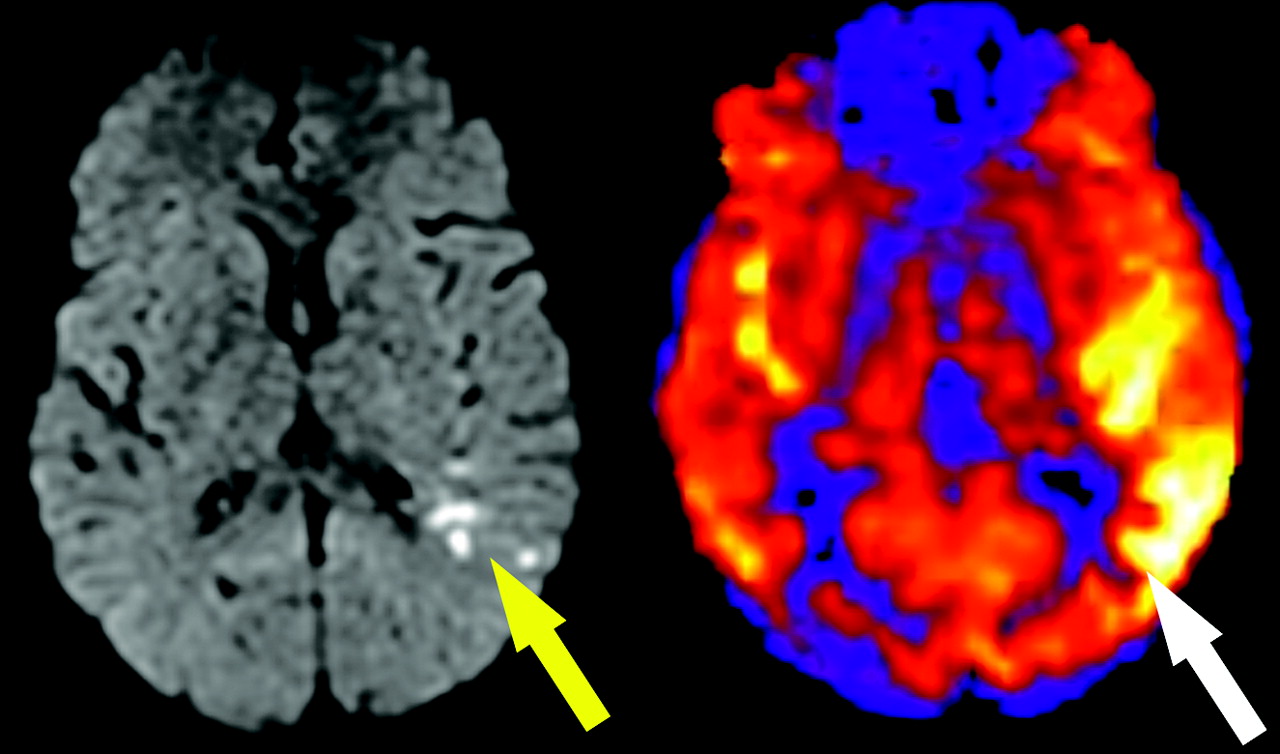

Hyperperfused stroke territory on ASL. A 73-year-old woman with atrial fibrillation and embolic infarcts in the left posterior cerebral artery and posterior watershed territories. Punctate areas of restricted diffusion are seen (left, yellow arrow). ASL map (right) shows gyral hyperperfusion in the left hemisphere (white arrow). Hypoperfusion is also seen in the right posterior watershed territory.